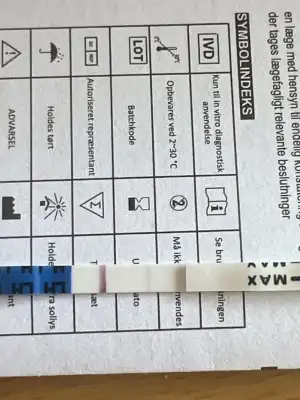

merhaba aranızda hiç ovülasyon veya çatlama gününde göğüslerinde kırmızı çatlak izleri oluşan oldu mu? ben en az 2 kez buna denk geldim ve lh testi ile doğruladım. beyaz çatlak izlerim zaten hep vardı ama ovülasyon gününde kıpkırmızı olup ertesi gün tekrar beyaz oluyorlar. böyle bir şey yaşayan var mı? :)